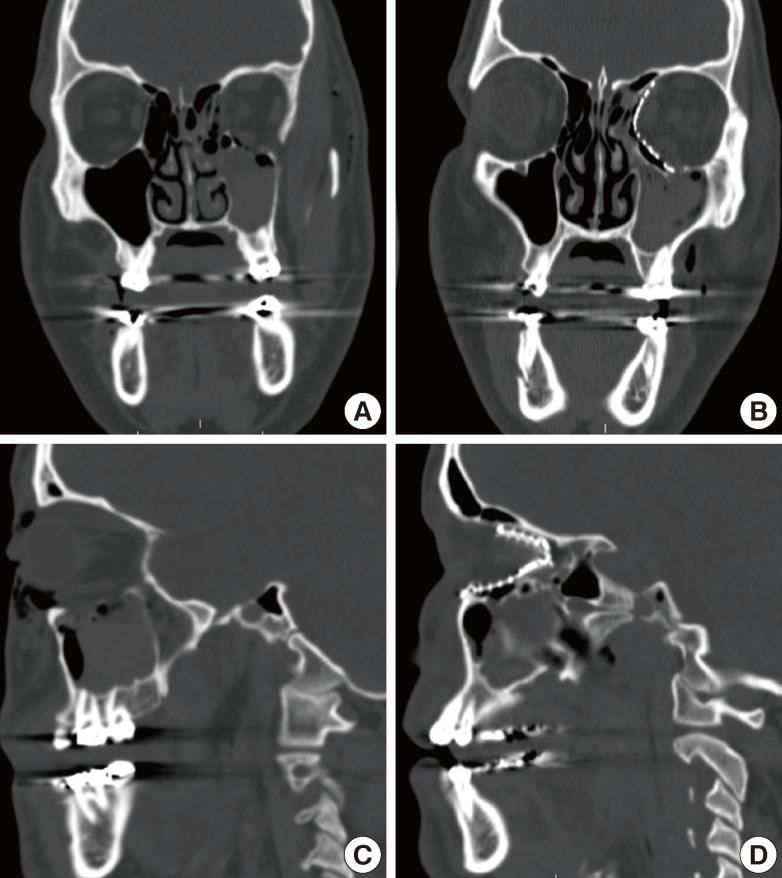

创伤后眼球内陷的矫正。

Correction of posttraumatic enophthalmos.

Management of posttraumatic enophthalmos can present as a challenge to the reconstructive surgeon, particularly in cases of late presentation. This article reviews the pertinent anatomy of the orbit, diagnostic modalities, indications for surgery, and surgical approaches as they relate to the treatment of posttraumatic enophthalmos. Internal orbital reconstruction has evolved to an elegant procedure incorporating various biologic or alloplastic implants, including anatomical pre-bent implants. Successful repair of late enophthalmos has been demonstrated in multiple recent studies and is likely related to the precision with which orbital anatomy can be restored.

创伤后眼球内陷的治疗对重建外科医生来说可能是一项挑战,尤其是在就诊较晚的病例中。本文回顾了眼眶的相关解剖结构、诊断方法、手术适应症以及与创伤后眼球内陷治疗相关的手术入路。眼眶内重建已发展成为一种精细的手术,采用各种生物或异体植入物,包括解剖学预弯植入物。最近的多项研究已证明晚期眼球内陷能够成功修复,这可能与眼眶解剖结构恢复的精确程度有关。